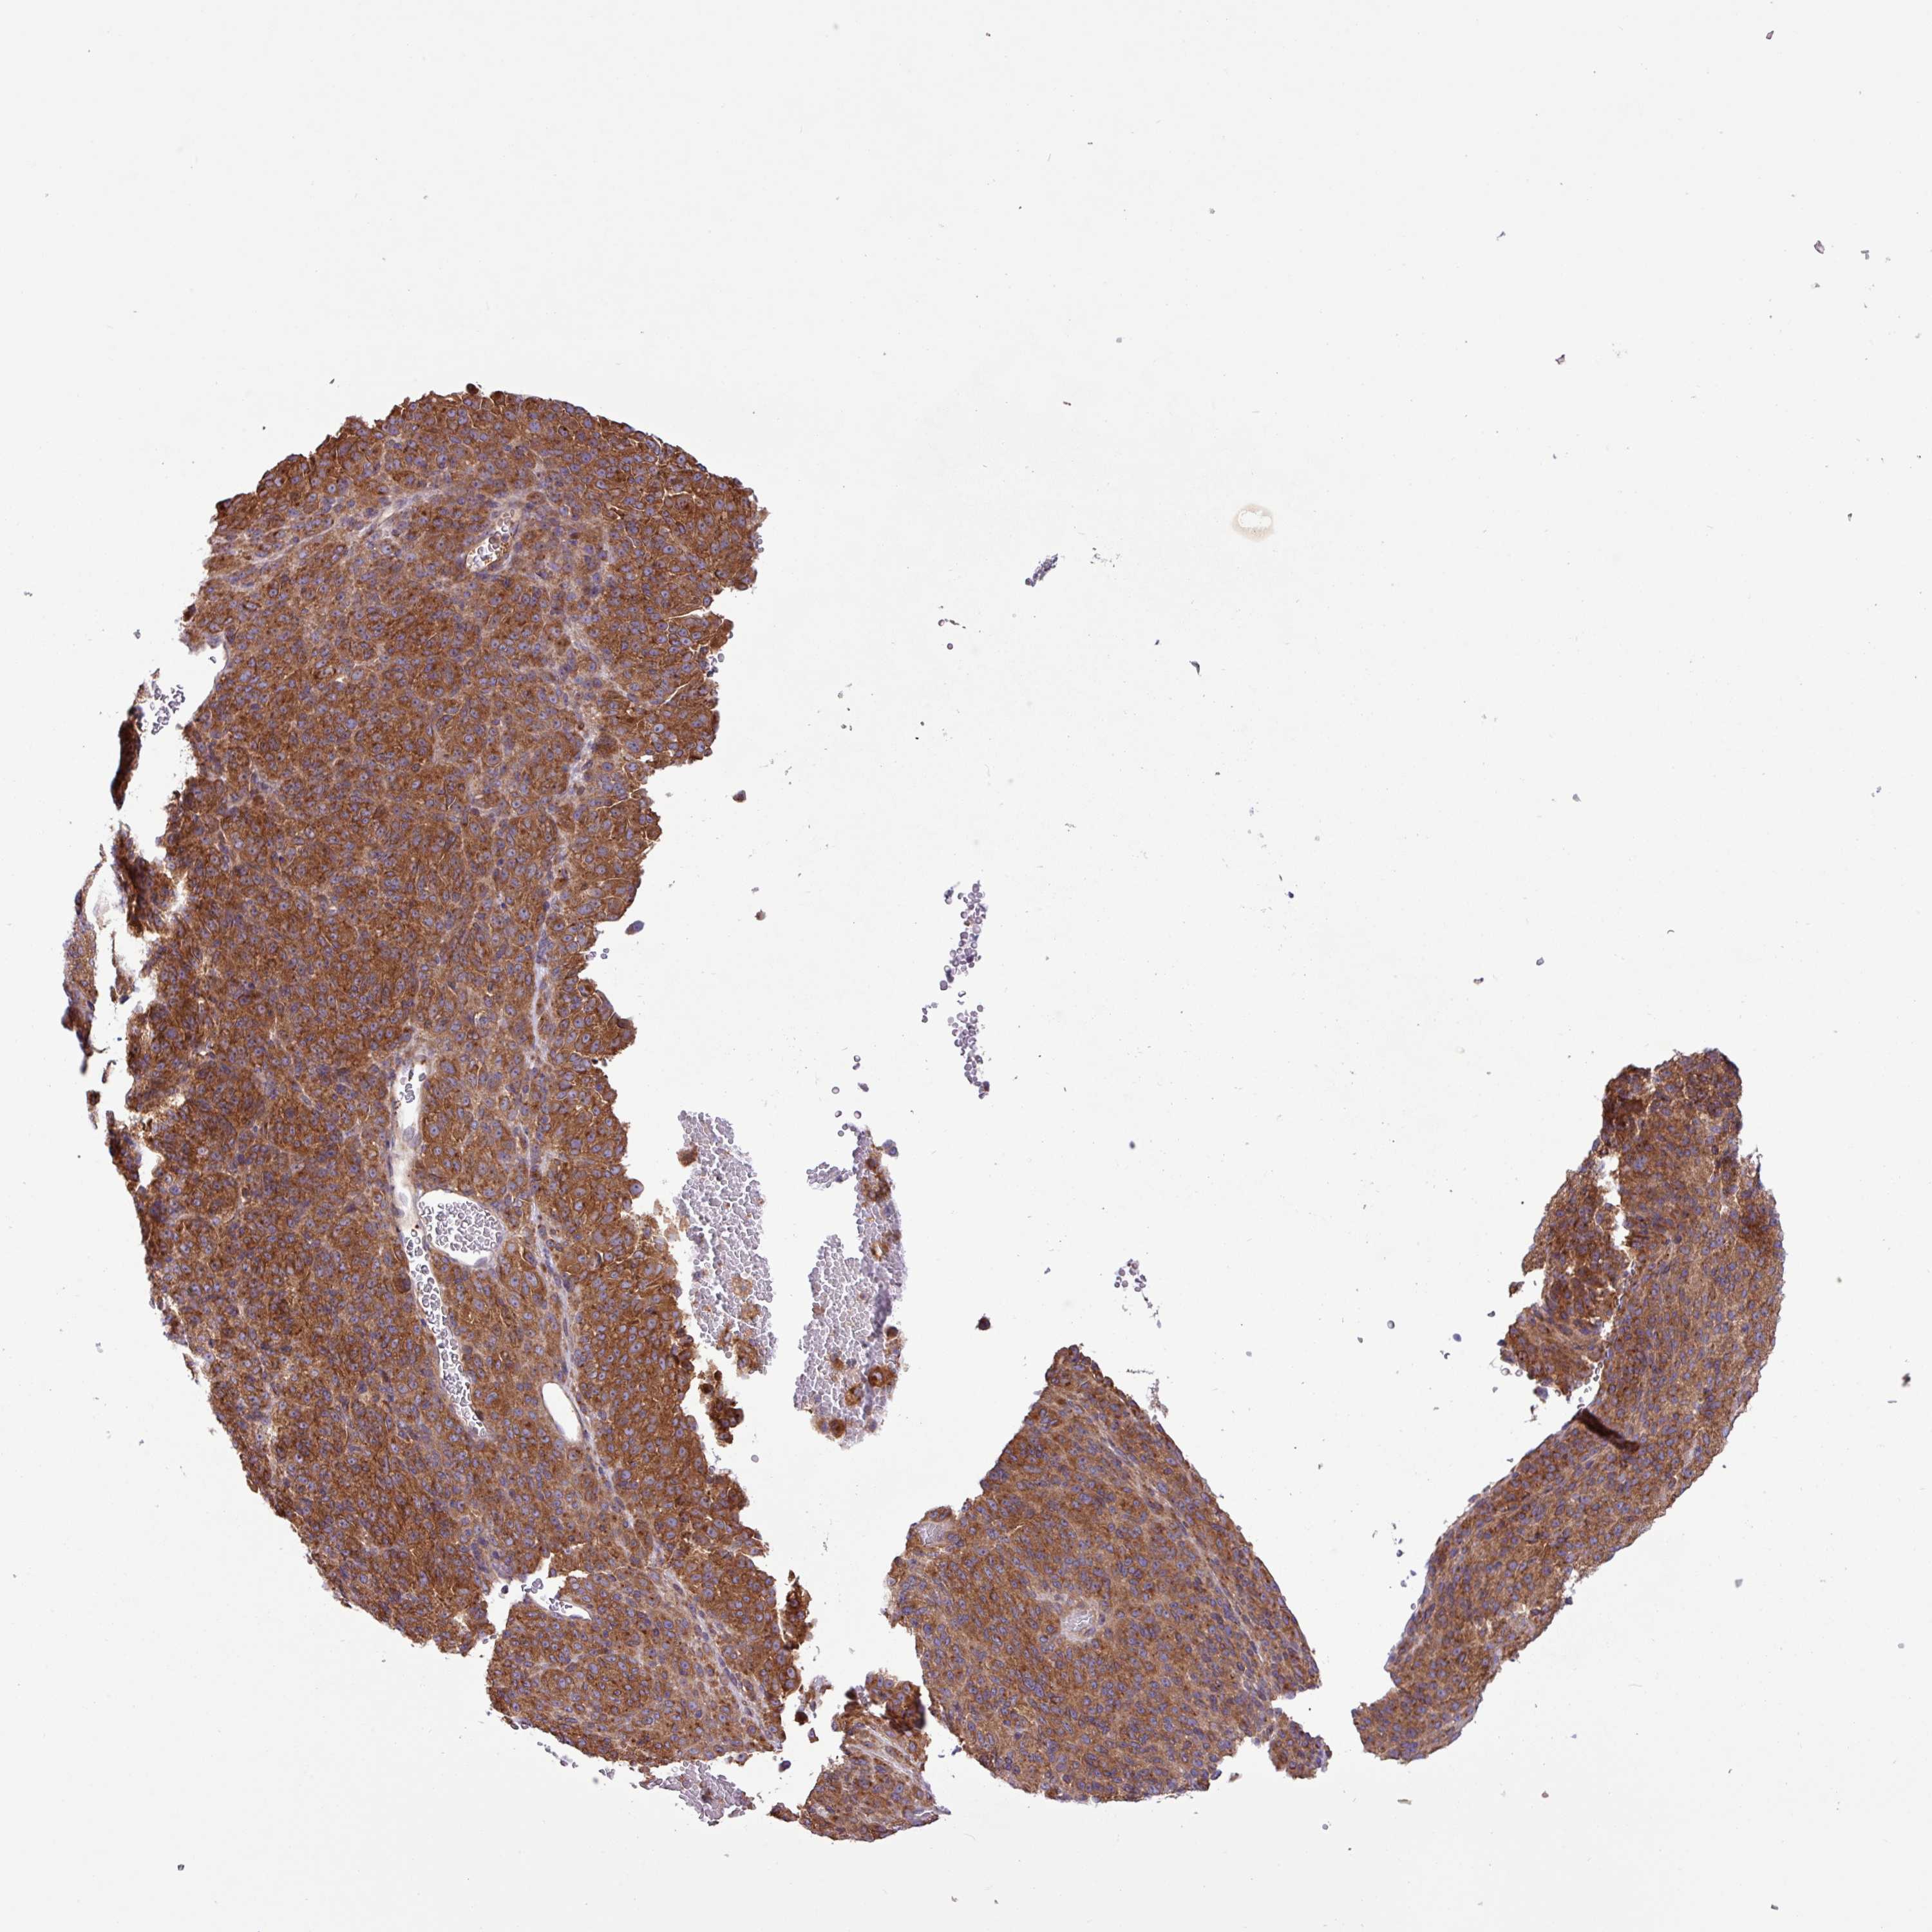

MELANOMA - Protein expressioni

A mouse-over function shows sample information and annotation data. Click on an image to view it in a full screen mode. Samples can be filtered based on level of antibody staining by selecting one or several of the following categories: high, medium, low and not detected. The assay and annotation is described here.

Note that samples used for immunohistochemistry by the Human Protein Atlas do not correspond to samples in the TCGA dataset.

Antibody stainingi

Antibody staining in the annotated cell types in the current human tissue is reported as not detected, low, medium, or high, based on conventional immunohistochemistry profiling in selected tissues. This score is based on the combination of the staining intensity and fraction of stained cells.

Each image is clickable and will lead to virtual microscopy that enables deeper exploration of all samples and also displays staining intensity scores, fraction scores and subcellular localization as well as patient and tissue information for each sample.

Antibody HPA051077

Staining

High

Medium

Low

Not detected

Intensity

Strong

Moderate

Weak

Negative

Quantity

>75%

75%-25%

<25%

None

Location

Nuclear

Cytoplasmic/membranous

Cytoplasmic/membranous,nuclear

Malignant melanoma, NOS

Malignant melanoma, Metastatic site